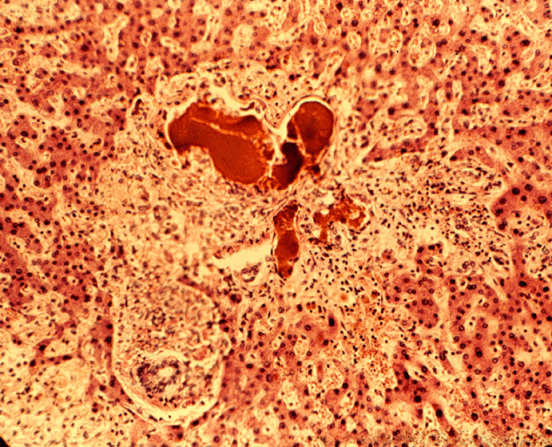

Саркома Капоши

Саркома Капоши может возникать на слизистой полости рта как в сочетании с изменениями на коже, так и без них. Высыпания на слизистой полости рта могут быть и первыми проявлениями болезни. Наиболее частая локализация высыпаний при саркоме Капоши — твердое и мягкое небо, резке они возникают на губах и на языке. Появляется опухолевидный узел размером от вишневой косточки до сливы, розовато-коричневого цвета, тестовидной консистенции, на поверхности которого и рядом с ним располагаются петехиальные элементы. Некоторые поражения могут сопровождаться изъязвлениями. Начальные проявления в виде красных, синеватых, фиолетовых пятен причиняют меньше беспокойства больным и обнаруживаются не сразу. Это заболевание часто выявляется у больных СПИДом. Решающее значение в диагностике имеют результаты гистологического исследования.

Саркома Капоши может возникать на слизистой полости рта как в сочетании с изменениями на коже, так и без них. Высыпания на слизистой полости рта могут быть и первыми проявлениями болезни. Наиболее частая локализация высыпаний при саркоме Капоши — твердое и мягкое небо, реже они возникают на губах и на языке. Появляется опухолевидный узел размером от вишневой косточки до сливы, розовато-коричневого цвета, тестовидной консистенции, на поверхности которого и рядом с ним располагаются петехиаль- ные элементы. Некоторые поражения могут сопровождаться изъязвлениями. Начальные проявления в виде красных, синеватых, фиолетовых пятен причиняют меньше беспокойства больным и обнаруживаются не сразу. Это заболевание часто выявляется у больных СПИДом. Решающее значение в диагностике имеют результаты гистологического исследования.